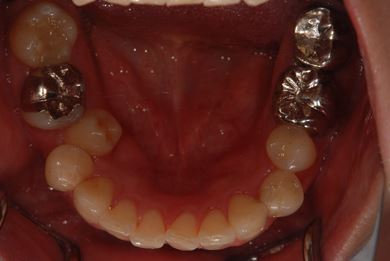

| 性別/年齢 | 女性 / 38歳 | ||||||||||||||||||||||||||||||||

| 主訴 | 右奥歯2本、インレーの相談をしたい。 | ||||||||||||||||||||||||||||||||

| 治療方針 | セラミック治療にて、審美的回復を行う。 | ||||||||||||||||||||||||||||||||

| 治療内容 | ハイブリッドセラミックインレー2本、メタルボンドセラミッククラウン2本(メタルボンド用土台2本)、オールセラミッククラウン1本(オールセラミック用土台1本) | ||||||||||||||||||||||||||||||||

| 総治療費 | 495,758円 | ||||||||||||||||||||||||||||||||

| 治療期間 | 1年6ヶ月 |